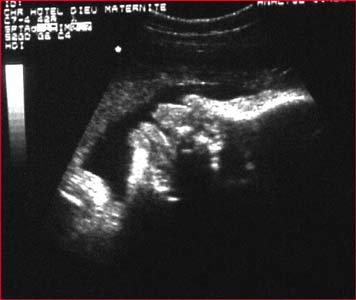

Langue : Zone échogène mobile